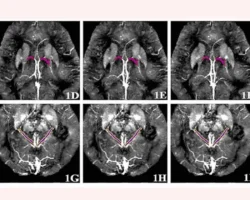

Команда российских исследователей предложила принципиально новый и уникальный подход, заключающийся в комплексном анализе состояния вен головного мозга с использованием магнитно-резонансной томографии с контрастированием и современных технологий машинного обучения. Если ранее специалисты ограничивались оценкой четырех вен, то новая технология учитывает параметры уже шести вен и их магнитной восприимчивости, что заметно повышает достоверность оценки.

Во время проведения процедуры пациенту внутрь организма вводят безопасный контраст на основе гадолиния, что обеспечивает максимально четкое отображение структуры сосудов. После МРТ специалисты измеряют параметры восприимчивости в шести венах, получая жизненно важные данные о состоянии кровоснабжения и насыщенности тканей кислородом. Именно эти показатели зачастую первыми изменяются при формировании ранних патологических процессов, свойственных болезни Альцгеймера.